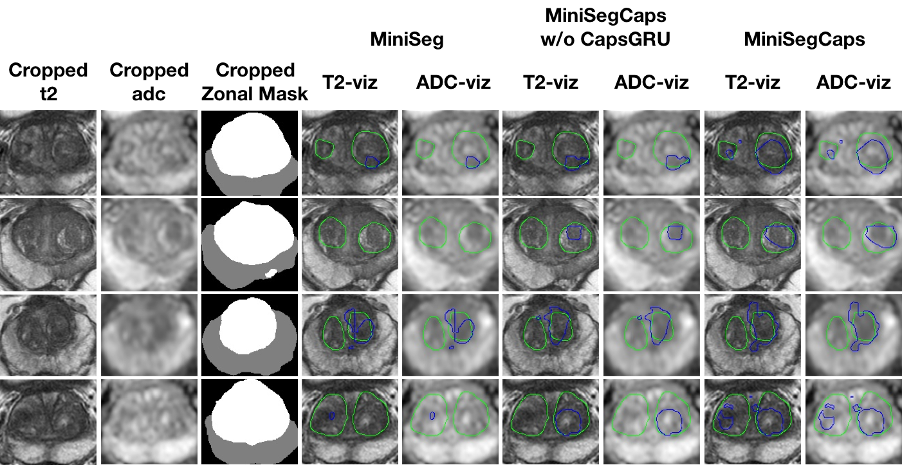

Fig.3 illustrates a visual comparison of the cropped T2, cropped ADC, cropped zonal mask, lesion ground truth, and predicted lesion mask by MiniSegCaps on T2 and ADC images. Our model successfully produced satisfactory segmentation of prostate cancer and revealed the spatial relationship between the zonal mask, lesion on T2, and ADC, which might help lesion location and classification. We also obtained consistent segmentations across adjacent slices within one volume, as shown in Fig.4. Our MiniSegCaps obtained better results than MiniSegCaps w/o CapsGRU, which indicates that CapsGRU captured the spatial information across adjacent slices as expected, boosting the prostate cancer segmentation performance. Moreover, our model achieved acceptable performance on BPH segmentation as shown in Fig.6.

Fig. 5. Visualization of benign nodule (e.g., BPH) segmentation results among different cases. The green contour is the ground truth, and the blue contours are from the deep learning predictions.